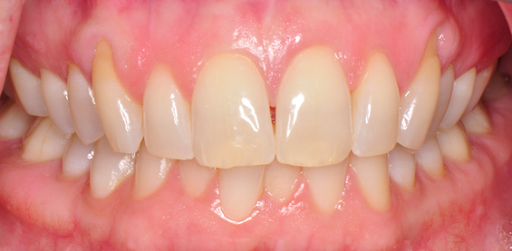

Close-up of teeth showing gingival recession on teeth #6 and #11.

Before

Close-up of a person's upper and lower teeth, showing gingival recession defects on #6 and #11 covered by gum grafts.

After